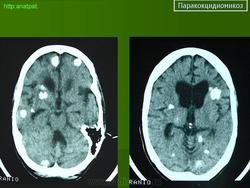

ГМ. Паракокцидиомикоз. +

Паракокцидиомикоз.

Множественные "узловые образования" имитирующие метастазы.